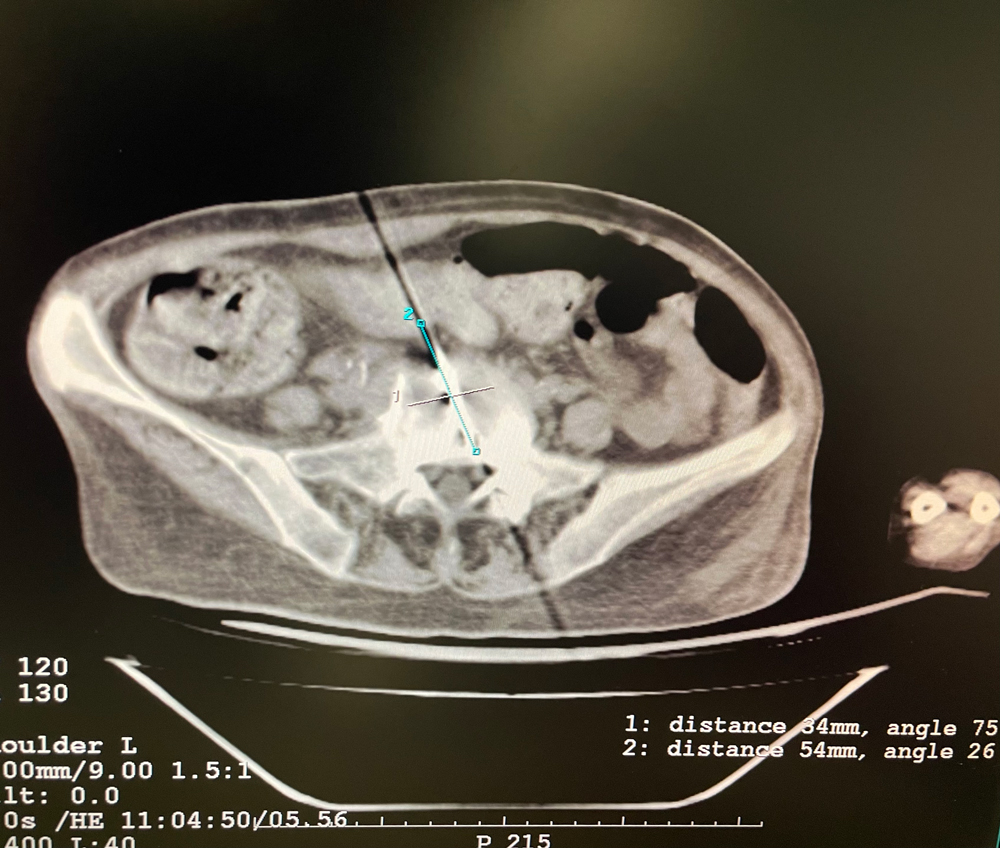

女,56歲,肺轉(zhuǎn)移瘤,骶骨、左側(cè)肋骨各一轉(zhuǎn)移灶,病灶大小均為5cm。骶骨轉(zhuǎn)移灶、肋骨轉(zhuǎn)移灶各進(jìn)行2個(gè)凍融循環(huán)。患者術(shù)后狀況良好。